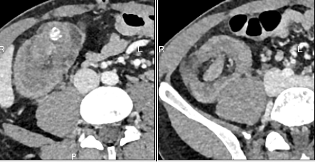

Coupe transverse

Les symptômes sont souvent aspécifiques, ce qui complique le diagnostic. Les patients peuvent se plaindre de douleurs abdominales intermittentes, de nausées, de vomissements ou présenter un tableau d’occlusion intestinale aiguë dans les formes avancées. Une hématochézie peut également survenir, bien que moins fréquente. Le diagnostic repose principalement sur l'imagerie. Le scanner abdominal est l'examen de choix, avec une sensibilité dépassant 90%, montrant des images caractéristiques en "cible ou donut" ou en "sandwich" selon l’orientation de la coupe. L'échographie, bien que moins fréquemment utilisée chez l'adulte, peut révéler des signes similaires. La coloscopie est utile pour identifier une éventuelle lésion tumorale.